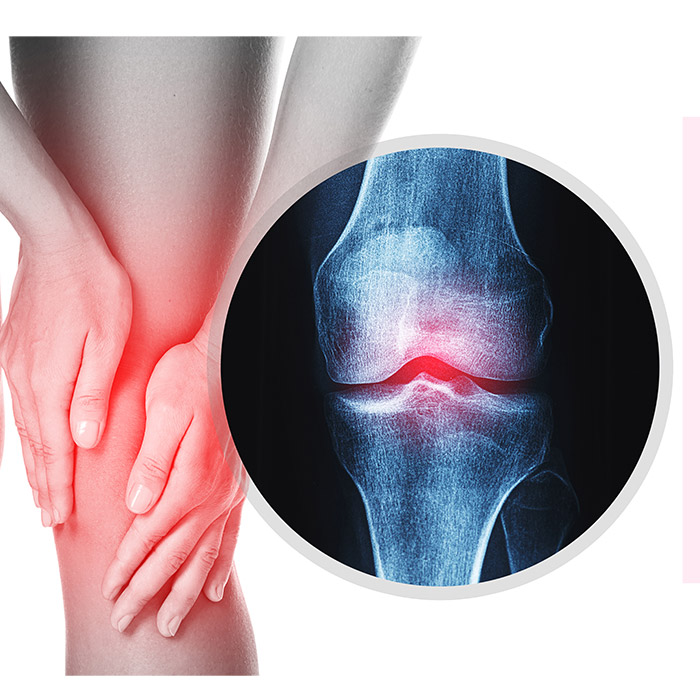

Torção do Joelho

Uma ligação frágil. Basta um movimento em falso para que ela ocorra. A torção do joelho pode ser mais frequente do que se imagina e causar problemas. E você deve saber o que fazer.

Mesmo não sendo a lesão mais frequente, a torção ou entorse do joelho pode esconder problemas, muitas vezes mais complicados. Em geral, ela ocorre porque os ligamentos são alongados e acabam se rompendo. Assim, quando o corpo gira sobre o pé apoiado ou se alguma coisa ou alguém atinge o joelho pelo lado de fora, ocorre a lesão nos ligamentos do lado de dentro, normalmente os mais afetados nestas circunstâncias.